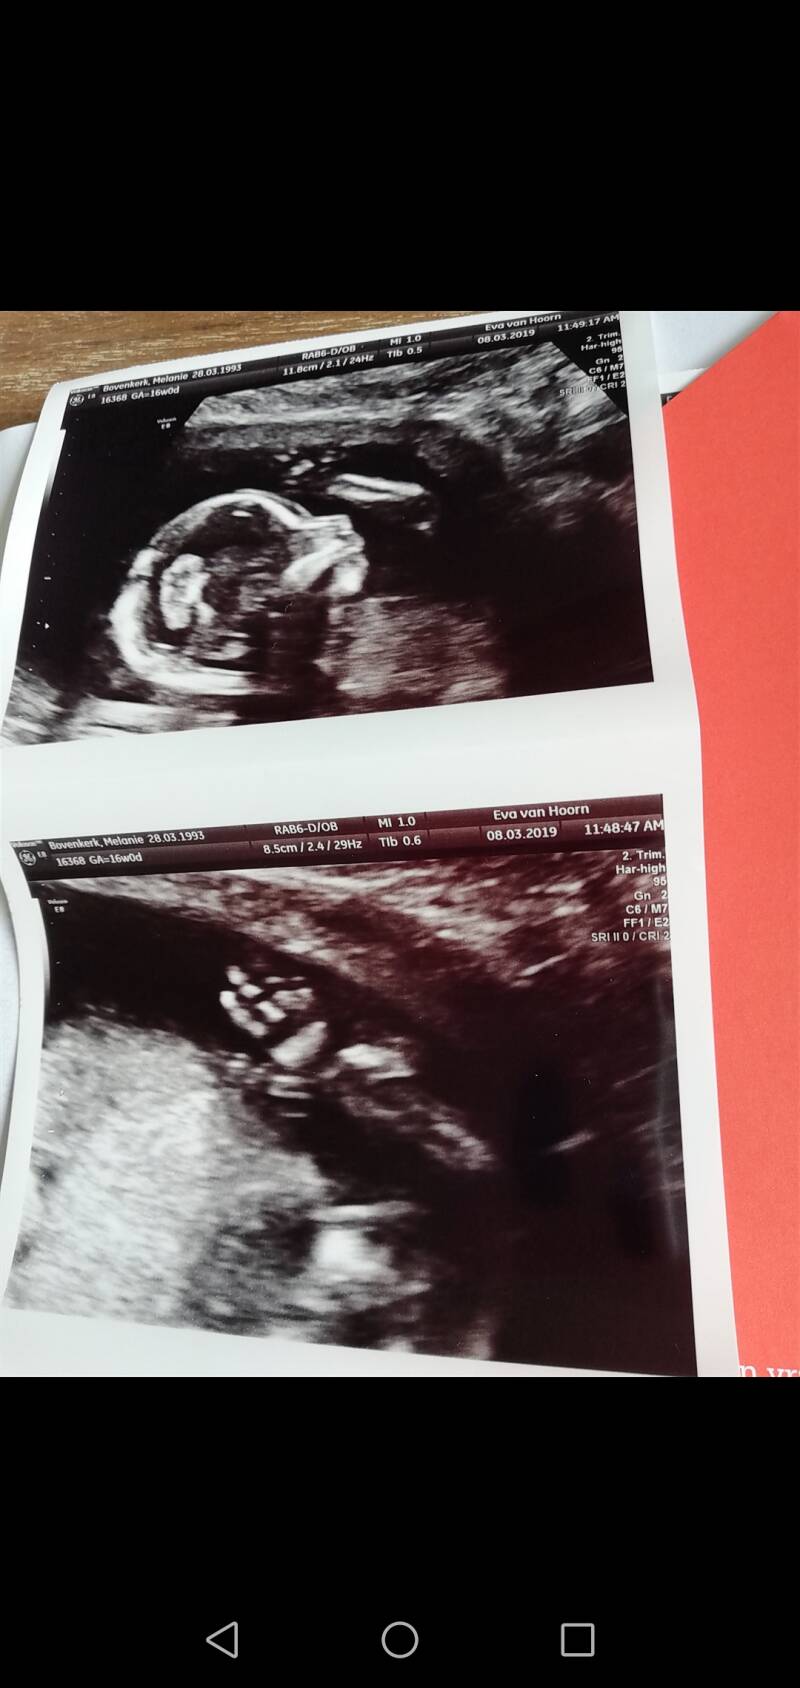

EINDELIJK.. 7 januari, de echo. Een kloppend hartje, een goeie ligging, alles zag er goed uit en ik was 7 weken zwanger. Het kan me allemaal niet snel genoeg gaan. 25 augustus ben ik uitgerekend, bij Aiden was dat 28 augustus....

22 januari had ik een intake bij de verloskunde praktijk Eva van Hoorn, en ook weer een echo. Deze echo was zo bijzonder. Wij zagen iets wat we nog nooit gezien hadden. De echo werd op mijn buik gezet en de eerste paar seconden waren we naar een kleine super ninja aan het kijken die wild om zich heen aan het spartelen was. Een super bewegelijk kindje. Dit was voorzichtig aangenomen een goed teken. Maar zonder de uitslag van het onderzoek zijn aannames dodelijk.